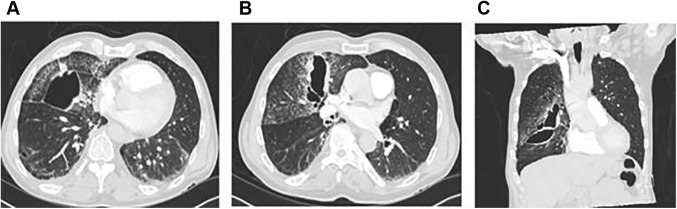

李主任对小刘医生说:“你看这个病人啊,就是典型的创伤性肺假性囊肿(TPP)。这个在临床可不算多见,你仔细看看王大爷的片子多学学吧!”

果然几个月后,王大爷来复查CT,肺部阴影消退得一干二净。

同时符合以下特征,即可初步诊断 TPP:①胸部高速钝性损伤史或穿透性胸外伤。②胸部CT或胸部X线片检查肺部气性空洞或液气性空洞。③伤前无特殊病史,近期影像检查无阳性发现,排除其他空洞性病变。[2]

在胸部X线检查中,TPP有高达50%的漏诊概率。胸部CT扫描是TPP的最佳检查方式,可以清晰地显示气/液平并更好地估计假性囊肿的数量、大小和位置。[1]

在需要机械通气的 TPP 患者中,假性囊肿可能会进展并导致血流动力学不稳定和/或压力增加引起的囊肿破裂引起的继发性气胸。在这种情况下,可能需要放置胸导管,使用胸腔镜手术或外科手术切除病变。降低呼气量和呼气末正压通气可能有助于预防气胸,但是还需要进一步的研究来为TPP患者建立最合适的机械通气治疗方案。TPP病变大多会随着时间的推移而缩小,通常在2-4个月内消退。[1]